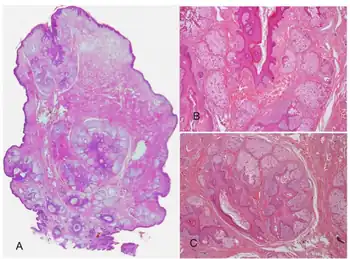

Folliculosebaceous cystic hamartoma abbreviated as (FSCH) is a rare cutaneous hamartoma consisting of dilated folliculosebaceous units invested in mesenchymal elements.[1]: 676 it typically affects adults, have a predilection for the central face or scalp, with less than 1.5 cm dimension.[2] Clinically, the lesions are asymptomatic, rubbery to firm in consistency, and usually occur on or above the neck in (> 90%) of cases, Histopathologically, FSCH shares several similar features to sebaceous trichofolliculoma, but it is usually possible to differentiate these two tumors.[3]